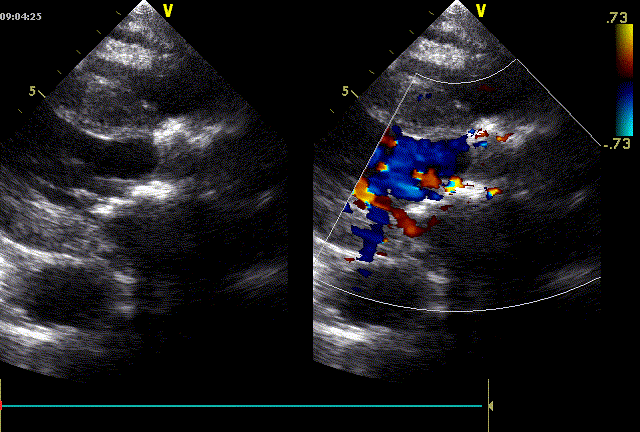

心脏超声示:主动脉瓣重度狭窄伴轻度关闭不全;二尖瓣中度狭窄伴轻度关闭不全;三尖瓣轻度反流;心包积液(少量)。

近日,中国人民解放军南部战区总医院王显悦教授、张本教授团队应用J-VALVE瓣膜完成一例高难度经心尖TAVI。患者为72岁男性,心脏超声示主动脉瓣重度狭窄伴轻度关闭不全,且二尖瓣中度狭窄。由于具有急性心力衰竭、高血压3级、肺气肿等其他疾病,且体重仅35公斤,对外科开胸手术耐受较差,风险极大,经过团队综合评估,决定行经心尖TAVI手术,拟植入25mm J-VALVE瓣膜。该患者存在升主动脉瓷化和左室流出道重度钙化,为手术增加了额外难度,术者团队凭借过硬的专业技能和细节处理能力,有效避免了术中可能存在的风险,并成功植入瓣膜。术后食道超声示无瓣周漏、无冠脉堵塞等并发症,患者症状明显缓解,手术顺利完成。